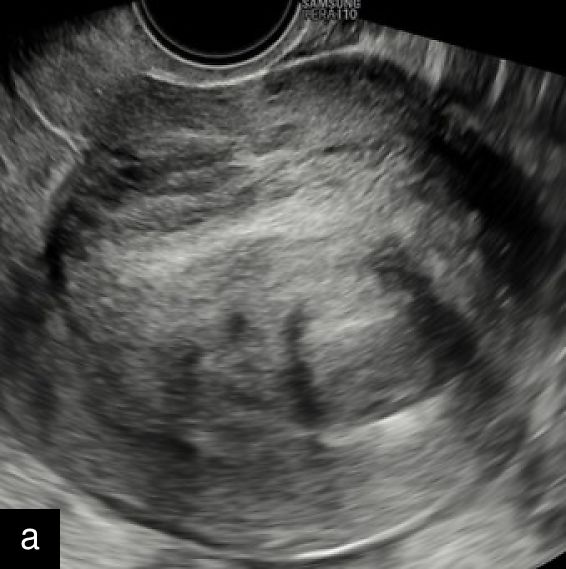

1

Transvaginal ultrasound images with Doppler evaluation of cases of STUMP. The images depict heterogeneous echotexture, irregular vascularization patterns and varying degrees of cystic and solid components.